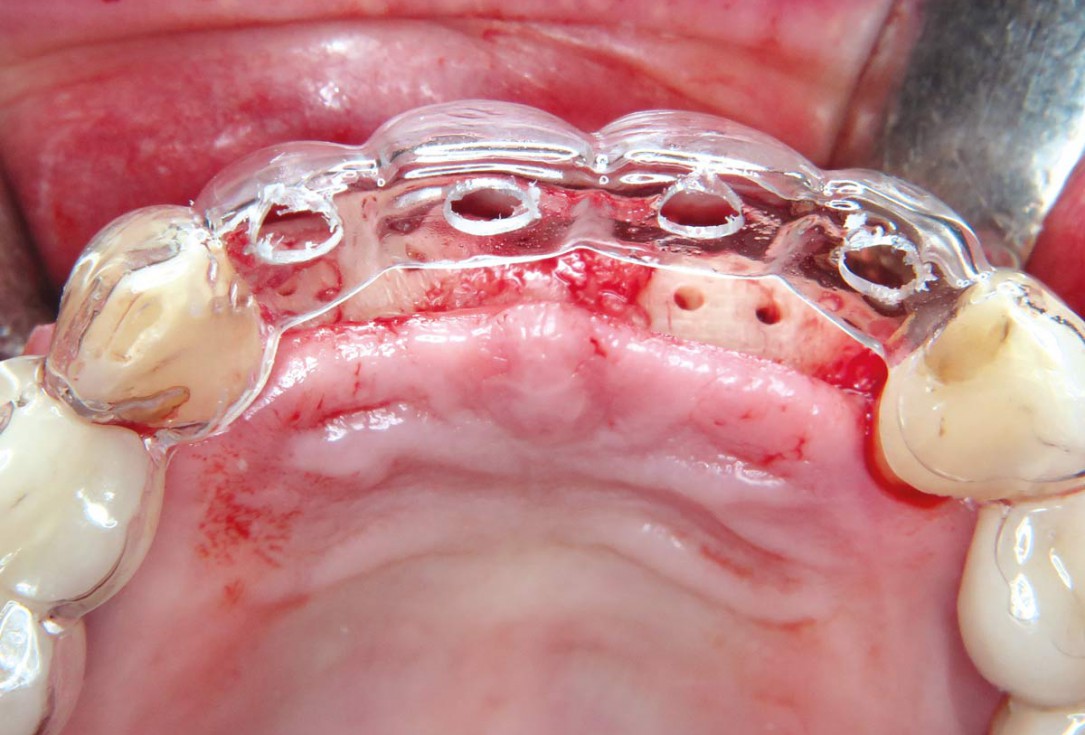

16 / 22 - Application of a drilling template for optimal implant positioning